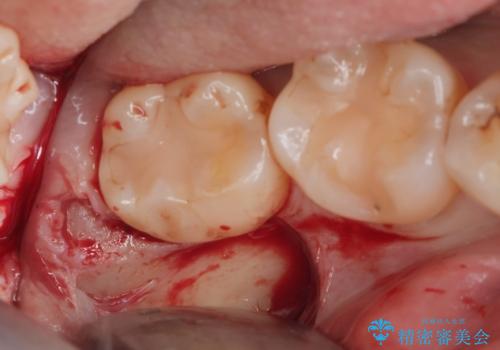

- 親知らずを抜歯したいとの事で来院。

パノラマ,CT撮影を行い安全なことを確認して抜歯を行いました。

抜歯後1週間後に抜糸と消毒を行い処置は完了になります。